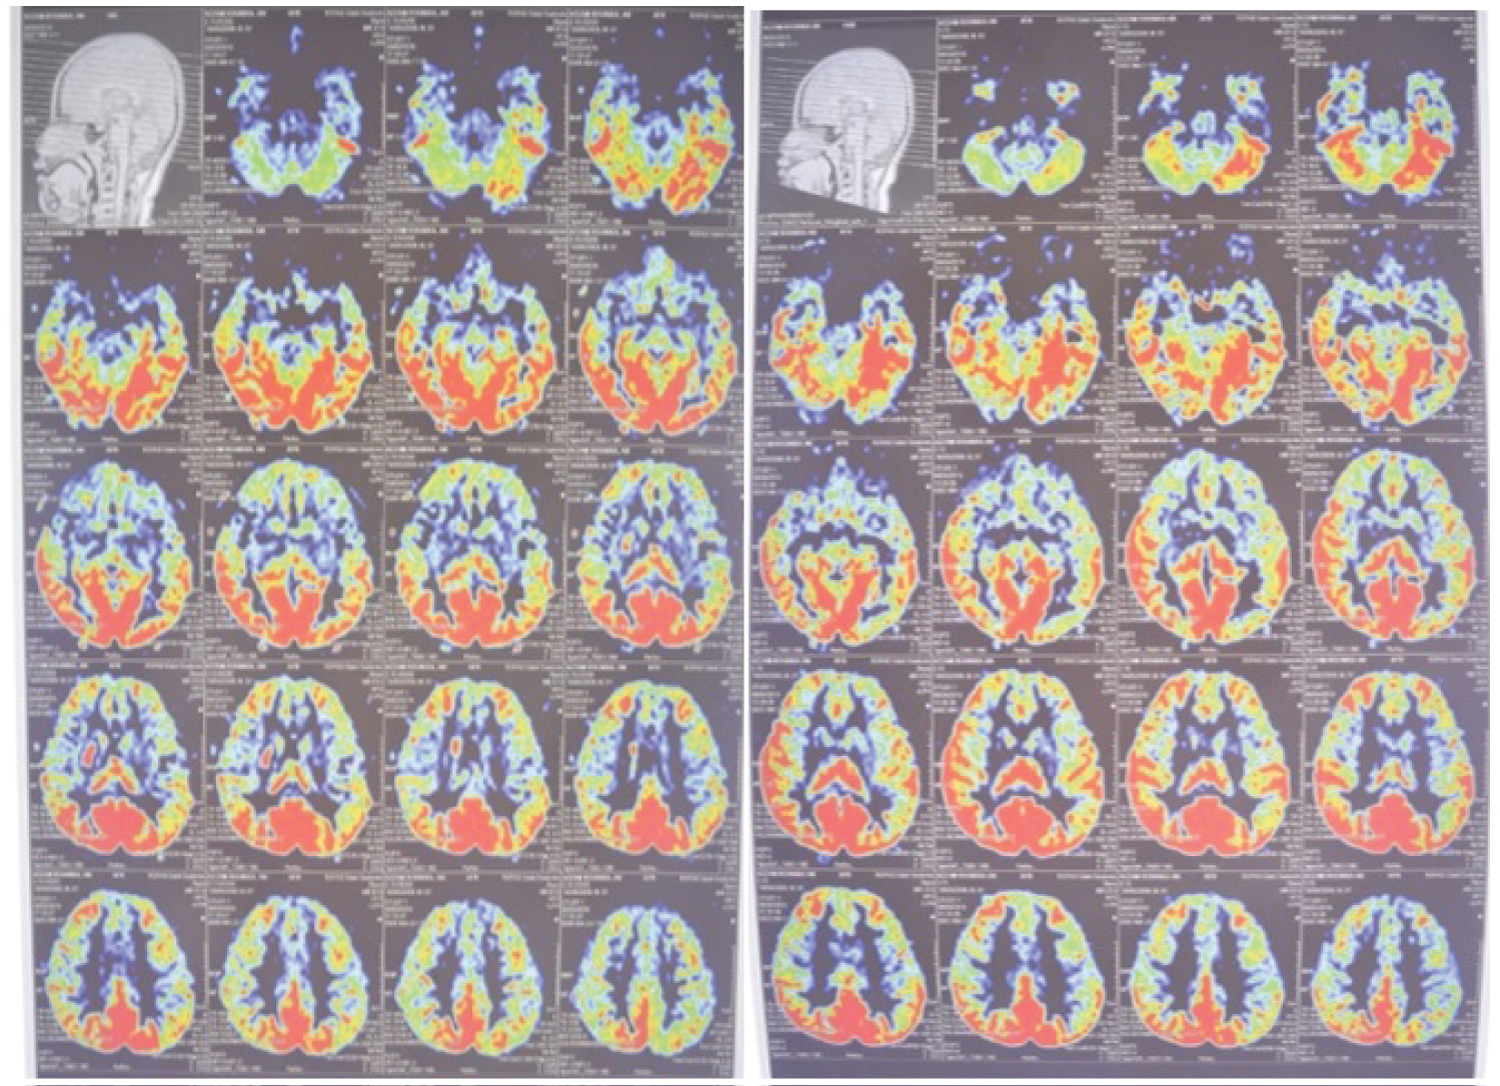

Elective Cerebral Digital Subtraction Angiography followed by Intra Arterial Heparin Flushing (IAHF) was performed. After this treatment, we found direct improvement in left sided motor function. He was able to raise his left hand over his ear, his hand grips strength improved, and finger foot flexion a left foot plantar flexion was reduced. After 4 hours of observation, we performed perfusion MRI to compare brain perfusion before and after IAHF. Compared to pre-IAHF, we found increasing perfusion in cortical and subcortical area (Figure 6).

Figure 6: The perfusion image compared brain perfusion before (left) and after (right) IAHF. View Figure 6